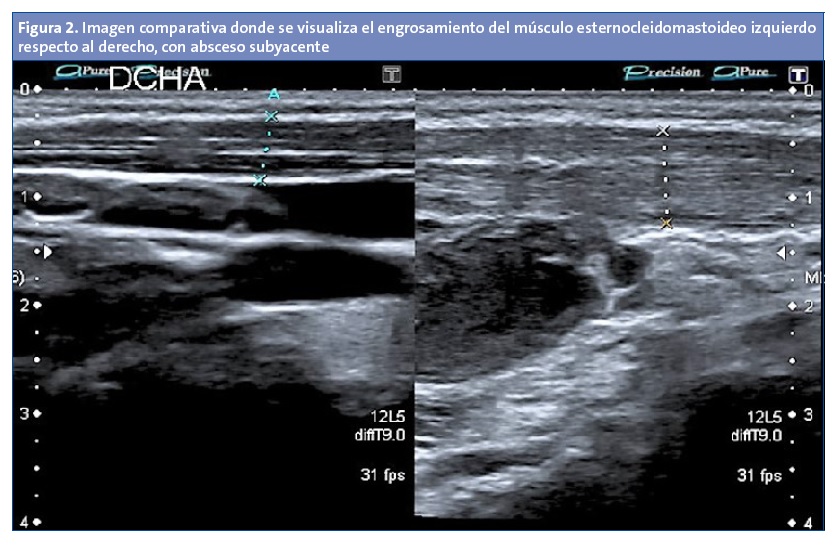

Tras una semana es revisada en consulta, persistiendo el dolor y la tumoración, esta vez indurada, sin otros síntomas acompañantes (Fig. 1), por lo que es derivada a Urgencias de su hospital de referencia, donde se le realiza una ecografía en la que se visualiza una lesión abscesificada subyacente al músculo esternocleidomastoideo (ECM), decidiéndose su ingreso para administrar tratamiento antibiótico intravenoso. Reexplorando a la paciente, se palpa el músculo ECM izquierdo engrosado en toda su extensión, por lo que se decide repetir la ecografía cervical de forma bilateral. El informe indica la presencia de un engrosamiento del músculo ECM izquierdo con respecto al derecho, con alteración de la ecogenicidad, visualizándose dos focos hipoecoicos intramusculares compatibles con piomiositis, así como la presencia de un absceso subyacente de 1,6 × 2,7 cm (Fig. 2).